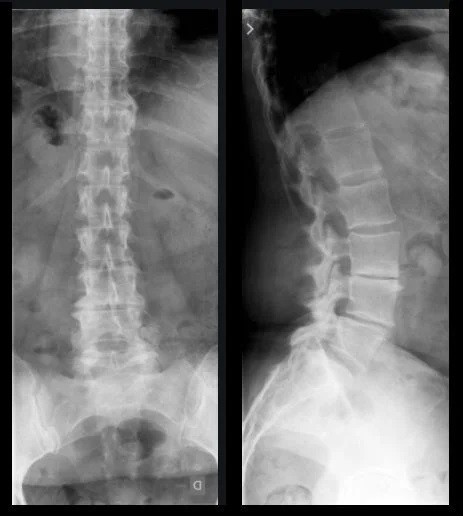

Raio X Lombar

Exame Raio X Lombo Sacra

O exame de Raio X Lombar é um procedimento radiológico fundamental para a avaliação da coluna lombar, região que suporta grande parte do peso corporal e está frequentemente sujeita a problemas como dores nas costas, hérnias de disco, e outras condições que podem impactar a mobilidade e a qualidade de vida dos colaboradores. Este exame fornece imagens detalhadas das vértebras lombares, permitindo a detecção precisa de anomalias, fraturas, degenerações e outras alterações que possam comprometer a saúde da coluna.